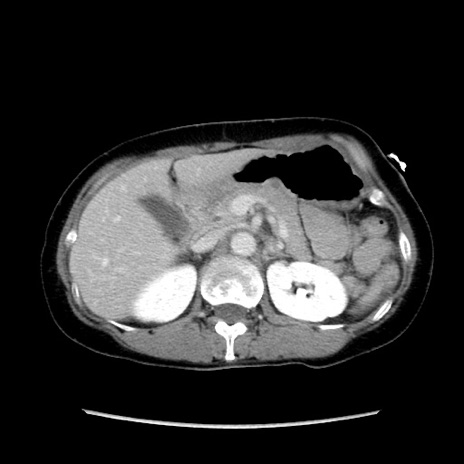

症例32(横断像)

【症例】40歳代 女性

【主訴】上腹部痛、嘔気・嘔吐

【現病歴】約9時間前頃から急に上腹部痛、嘔気、嘔吐が出現。改善しないため救急要請。

【既往歴】子宮頚癌(広汎子宮全摘術、放射線療法)、腸閉塞

【身体所見】腹部:平坦、軟、腸雑音亢進、上腹部を中心に腹部全体に圧痛あり。

【データ】WBC 8400、CRP 0.03